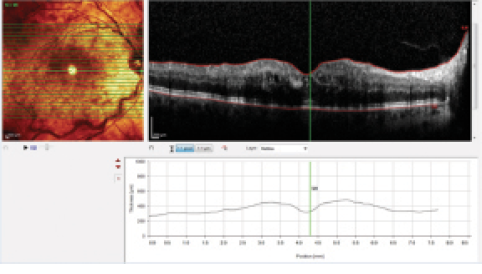

Figure 3. Same patient as seen in Figure 2. OCT shows cystoid macular edema. Visual acuity is 20/200.